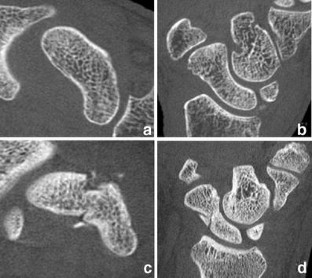

Flat-panel volume computed tomography (fpVCT) is a recent development in imaging. We discuss some of the musculoskeletal applications of a high-resolution flat-panel CT scanner. FpVCT has four main advantages over conventional multidetector computed tomography (MDCT): high-resolution imaging; volumetric coverage; dynamic imaging; omni-scanning. The overall effective dose of fpVCT is comparable to that of MDCT scanning. Although current fpVCT technology has higher spatial resolution, its contrast resolution is slightly lower than that of MDCT (5-10HU vs. 1-3HU respectively). We discuss the efficacy and potential utility of fpVCT in various applications related to musculoskeletal radiology and review some novel applications for pediatric bones, soft tissues, tumor perfusion, and imaging of tissue-engineered bone growth. We further discuss high-resolution CT and omni-scanning (combines fluoroscopic and tomographic imaging).